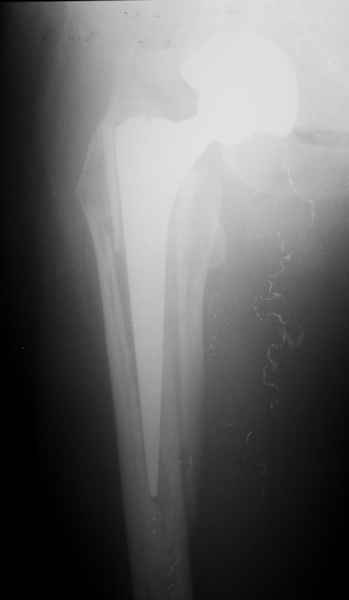

2. Применение ножки дистальной фиксации, мы отдаем предпочтение ножке Вагнера с фиксацией проксимального отдела на ножке. Более травматичное вмешательство, но при стабильной фиксации ножки реабилитация идет в обычном режиме.

Хочется показать два подобных случая, П-ка З. 72 лет и п-т Г. 80 лет. Сразу принимаю замечание, что это были ножки цементной фиксации, просто под руками не было бесцементника.